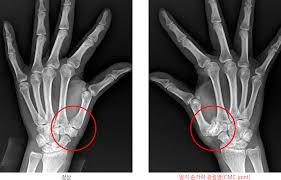

- 골관절염(Osteoarthritis): 연골 마모로 인해 관절이 뻑뻑하고 소리가 나기도 하며, 주로 DIP, PIP, 엄지뿌리 관절에 발생합니다 :contentReference[oaicite:2]{index=2}.